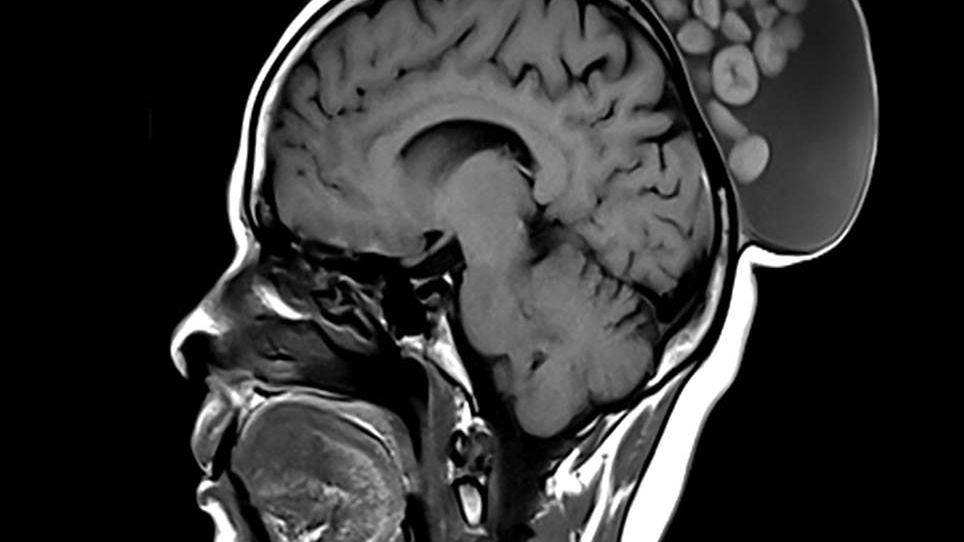

52-letnia kobieta zgłosiła się do lekarza z bezbolesnym guzem, który od czasu dzieciństwa pacjentki przez lata powiększał swój rozmiar. Badanie ujawniło, że ma on wymiary 15x10x12 cm. Wykonane badanie obrazowe MRI ujawniło dużą torbielowatą zmianę w płaszczyźnie podgałkowej skóry głowy, którą autorzy pracy porównali do "worka kulek". W opublikowanym na łamach "Radiology" obrazie MRI rzeczywiście widoczna jest okrągła torbiel wypełniona guzkami przypominającymi małe kulki.